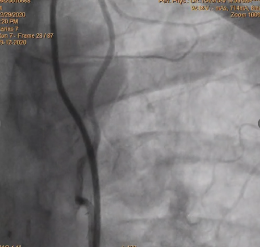

· TVD-Diffused disease- LAD, LCX& RCA

- SVG TO OM DLCX MID SEGMENT 90% Distally Near ANASTOMOSIS 80%

Planned SVG Stenting -OM and Distal LCX ,

stent was deployed in OM and LCX